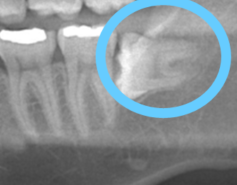

しかも、歯科ドクターが一番苦労するという下あごの親知らずで、かつ手前の歯に対して真横に生えてくるパターンでした(^^💦あら

▼こんなイメージです

残してもいいけれど、私の場合レントゲン画像の様に、

真横に生えてしまっているので、これがどんどん前に出てきてしまったら、前に生えている歯が押されてしまい、歯並びがずれてしまうかもしれない事、

そしてすでに隣接している歯との間に小さく虫歯ができてしまっているようでした。